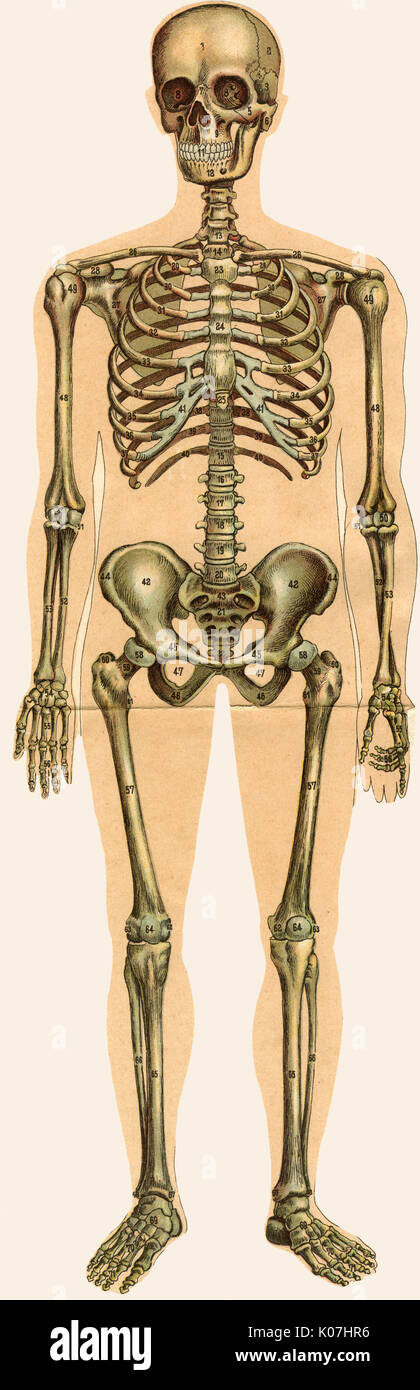

Männchen anatomie Stockfotos & Bilder

Suchergebnisse für Männchen anatomie Stock-Fotos & Bilder (86,080)